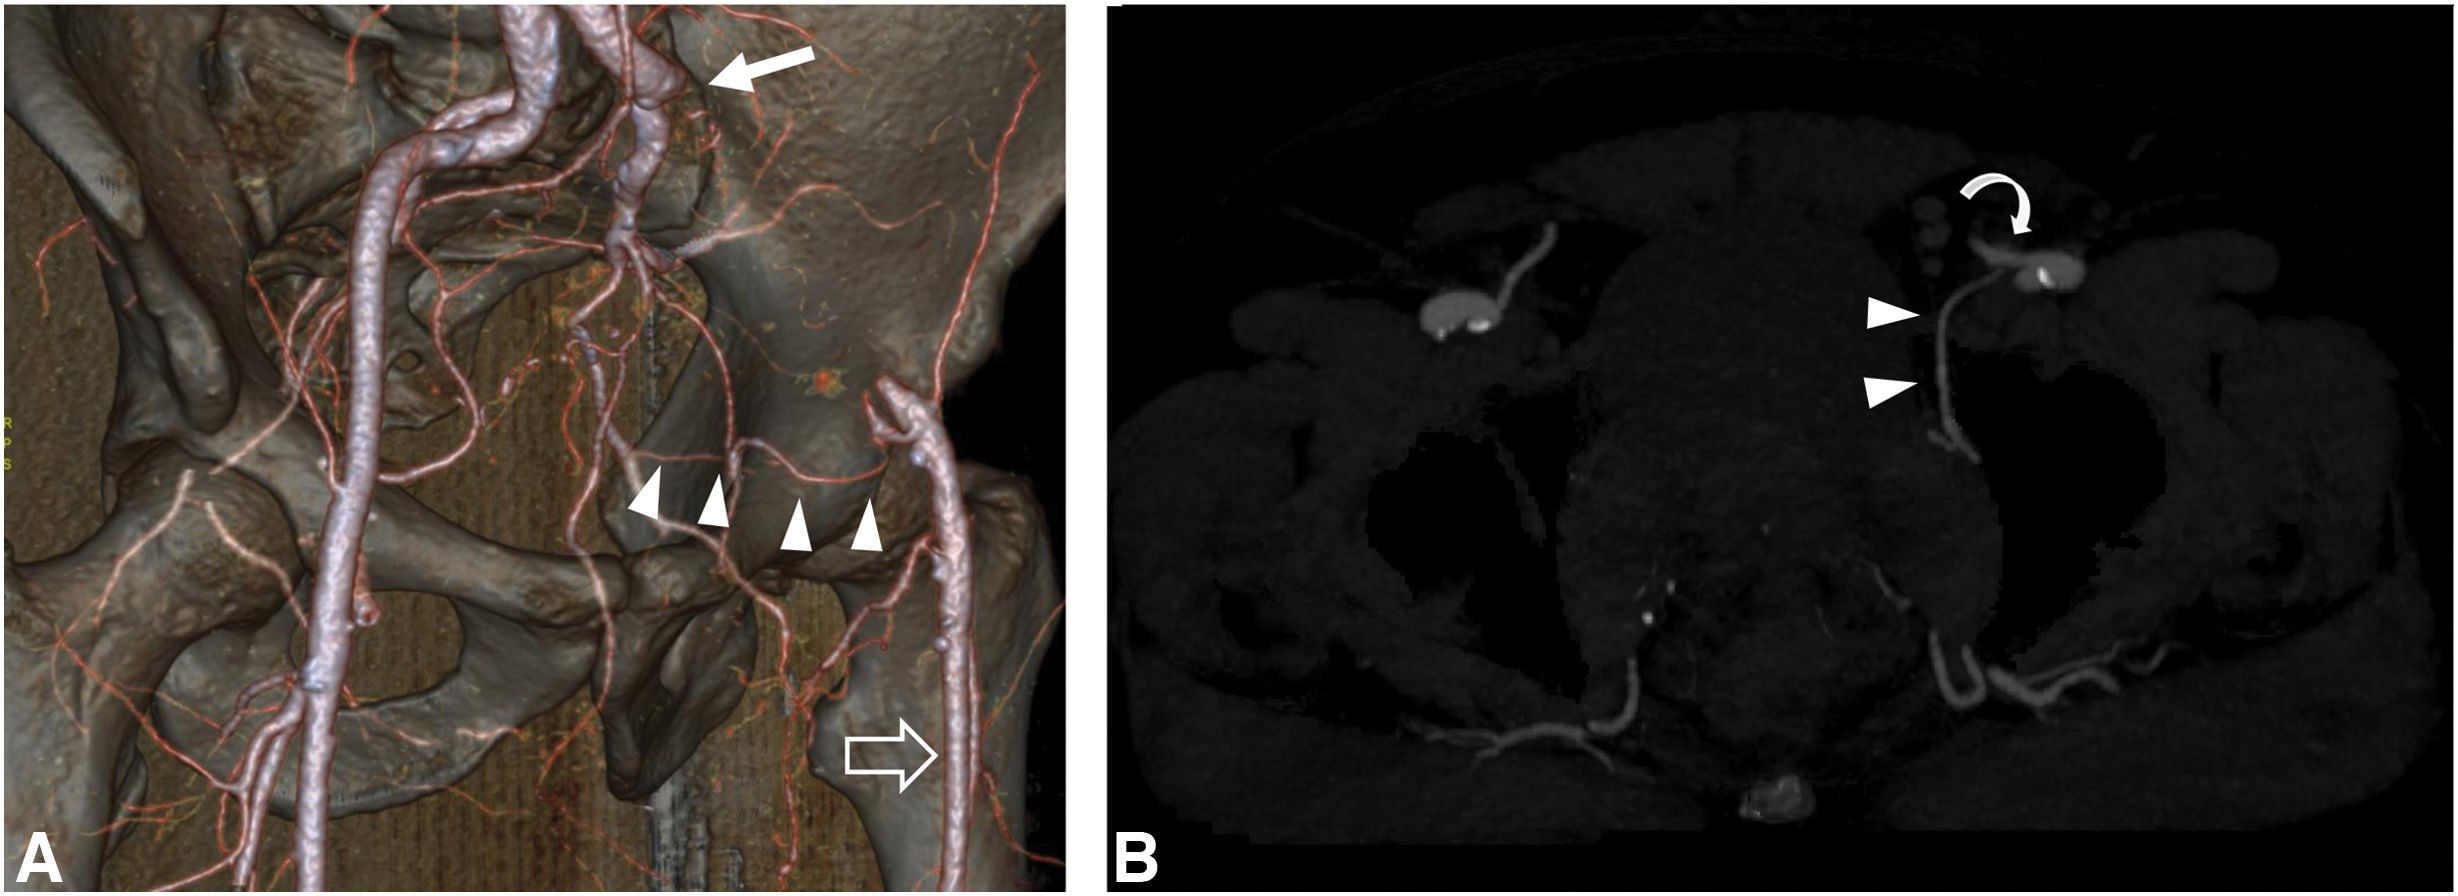

Corona mortis is a common vascular variant in the pelvis with significant clinical importance. While there is no standardised definition, the term generally refers to any anatomical situation where a vessel —either arterial or venous— crosses over the superior pubic ramus and is thus susceptible to injury. This anatomical course places it at high risk of injury in numerous clinical scenarios, including pelvic trauma and various surgical procedures. The aim of this article is to review the anatomy of arterial corona mortis using computed tomography angiography (CTA) and digital subtraction angiography and to use examples to illustrate the considerable clinical significance of this vascular variant. With its high prevalence and relevance, arterial corona stands out as the leading pelvic vascular variant. Radiologists should be familiar with its anatomy and high haemorrhagic risk, explicitly including it in radiological reports when the clinical situation means it could be of significance.